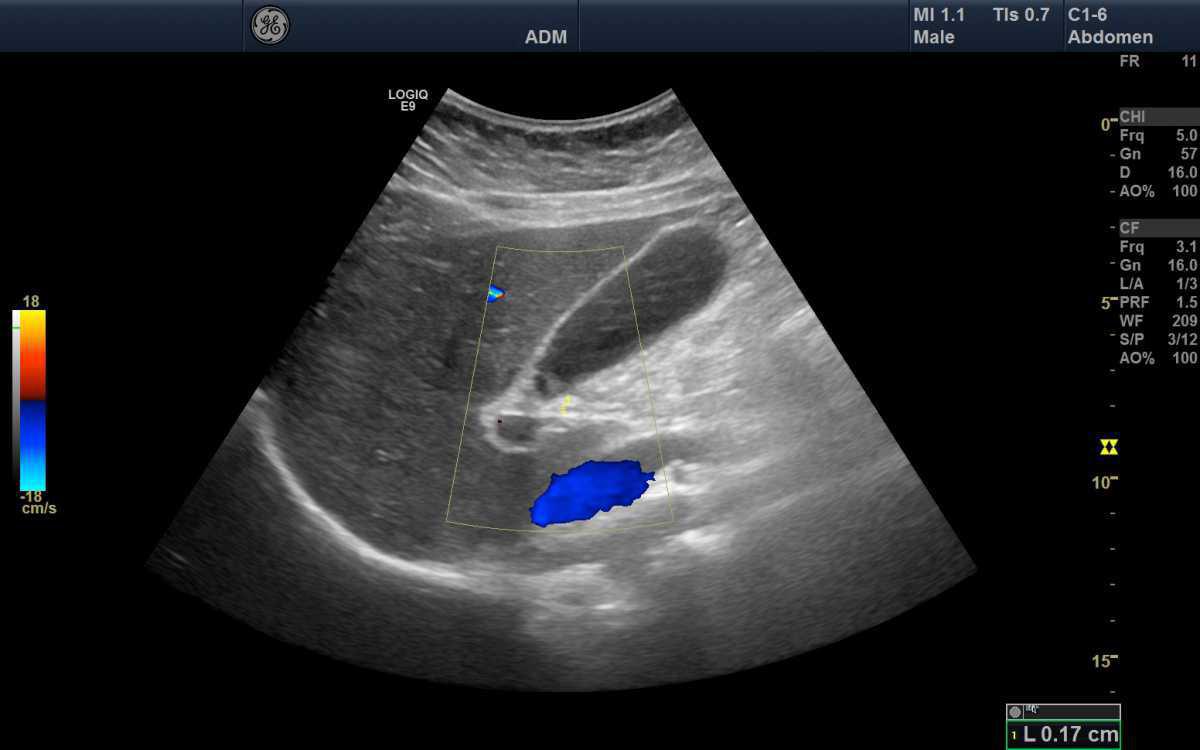

🧭 Fenêtres Acoustiques & Repères Anatomiques

L’examen débute souvent par la région sus-mésocolique, en utilisant le foie comme fenêtre acoustique principale.

Le parenchyme hépatique homogène permet d’identifier :

- La veine cave inférieure.

- Les veines sus-hépatiques.

- La vésicule biliaire.

🫀 Autres repères :

- Rate → explorée par voie intercostale gauche (avec le diaphragme comme repère supérieur).

- Reins → visualisés dans le plan longitudinal oblique postérieur.

- Vessie → observée en abaissant la profondeur pour explorer le pelvis.

💧 Recherche systématique du liquide libre :

- Espace hépato-rénal (de Morrison).

- Espace spléno-rénal.

- Récessus pelvien (cul-de-sac de Douglas chez la femme, vésico-rectal chez l’homme).

Le liquide libre apparaît anéchogène et suit toujours les espaces anatomiques déclives.